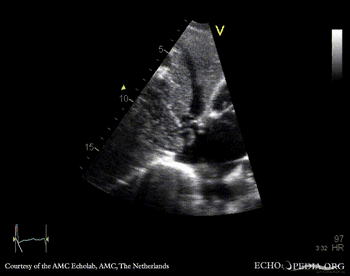

| Subcostal view | Subcostal view with color doppler |